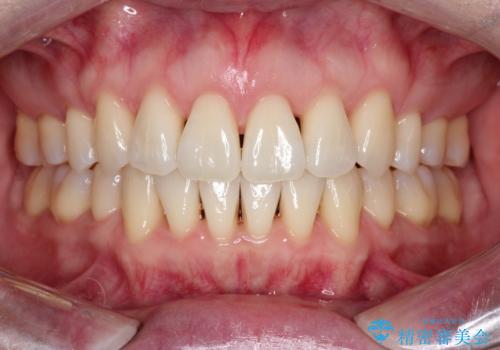

【抜歯ケース】前歯のガタガタをインビザラインで治療

- 前歯のガタガタを主訴に来院されました。

抜歯が必要なケースでしたが、インビザラインでの治療を希望されワイヤーを使用せずに治療を完了しております。

抜歯を伴う矯正治療はマウスピース矯正よりもワイヤー矯正の方がメリットが多いです。当院で抜歯を伴うマウスピース矯正を希望される場合は、場合によってワイヤーを使うことを了承していただいた上で治療を行なっています。